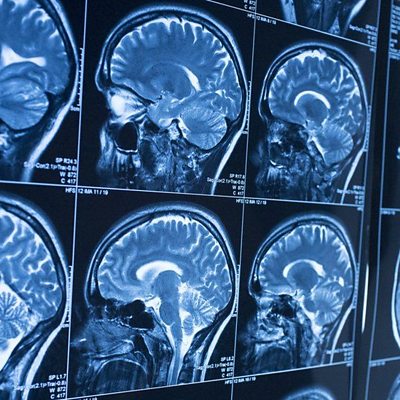

A woman from Saffron Walden who has two brain tumours is raising money for research into the condition. Cindy White is living with two brain tumours after having had another removed at Addenbrookes Hospital in Cambridge, and will be doing at least ten thousand steps every day of February to raise money for Brain Tumour Research.